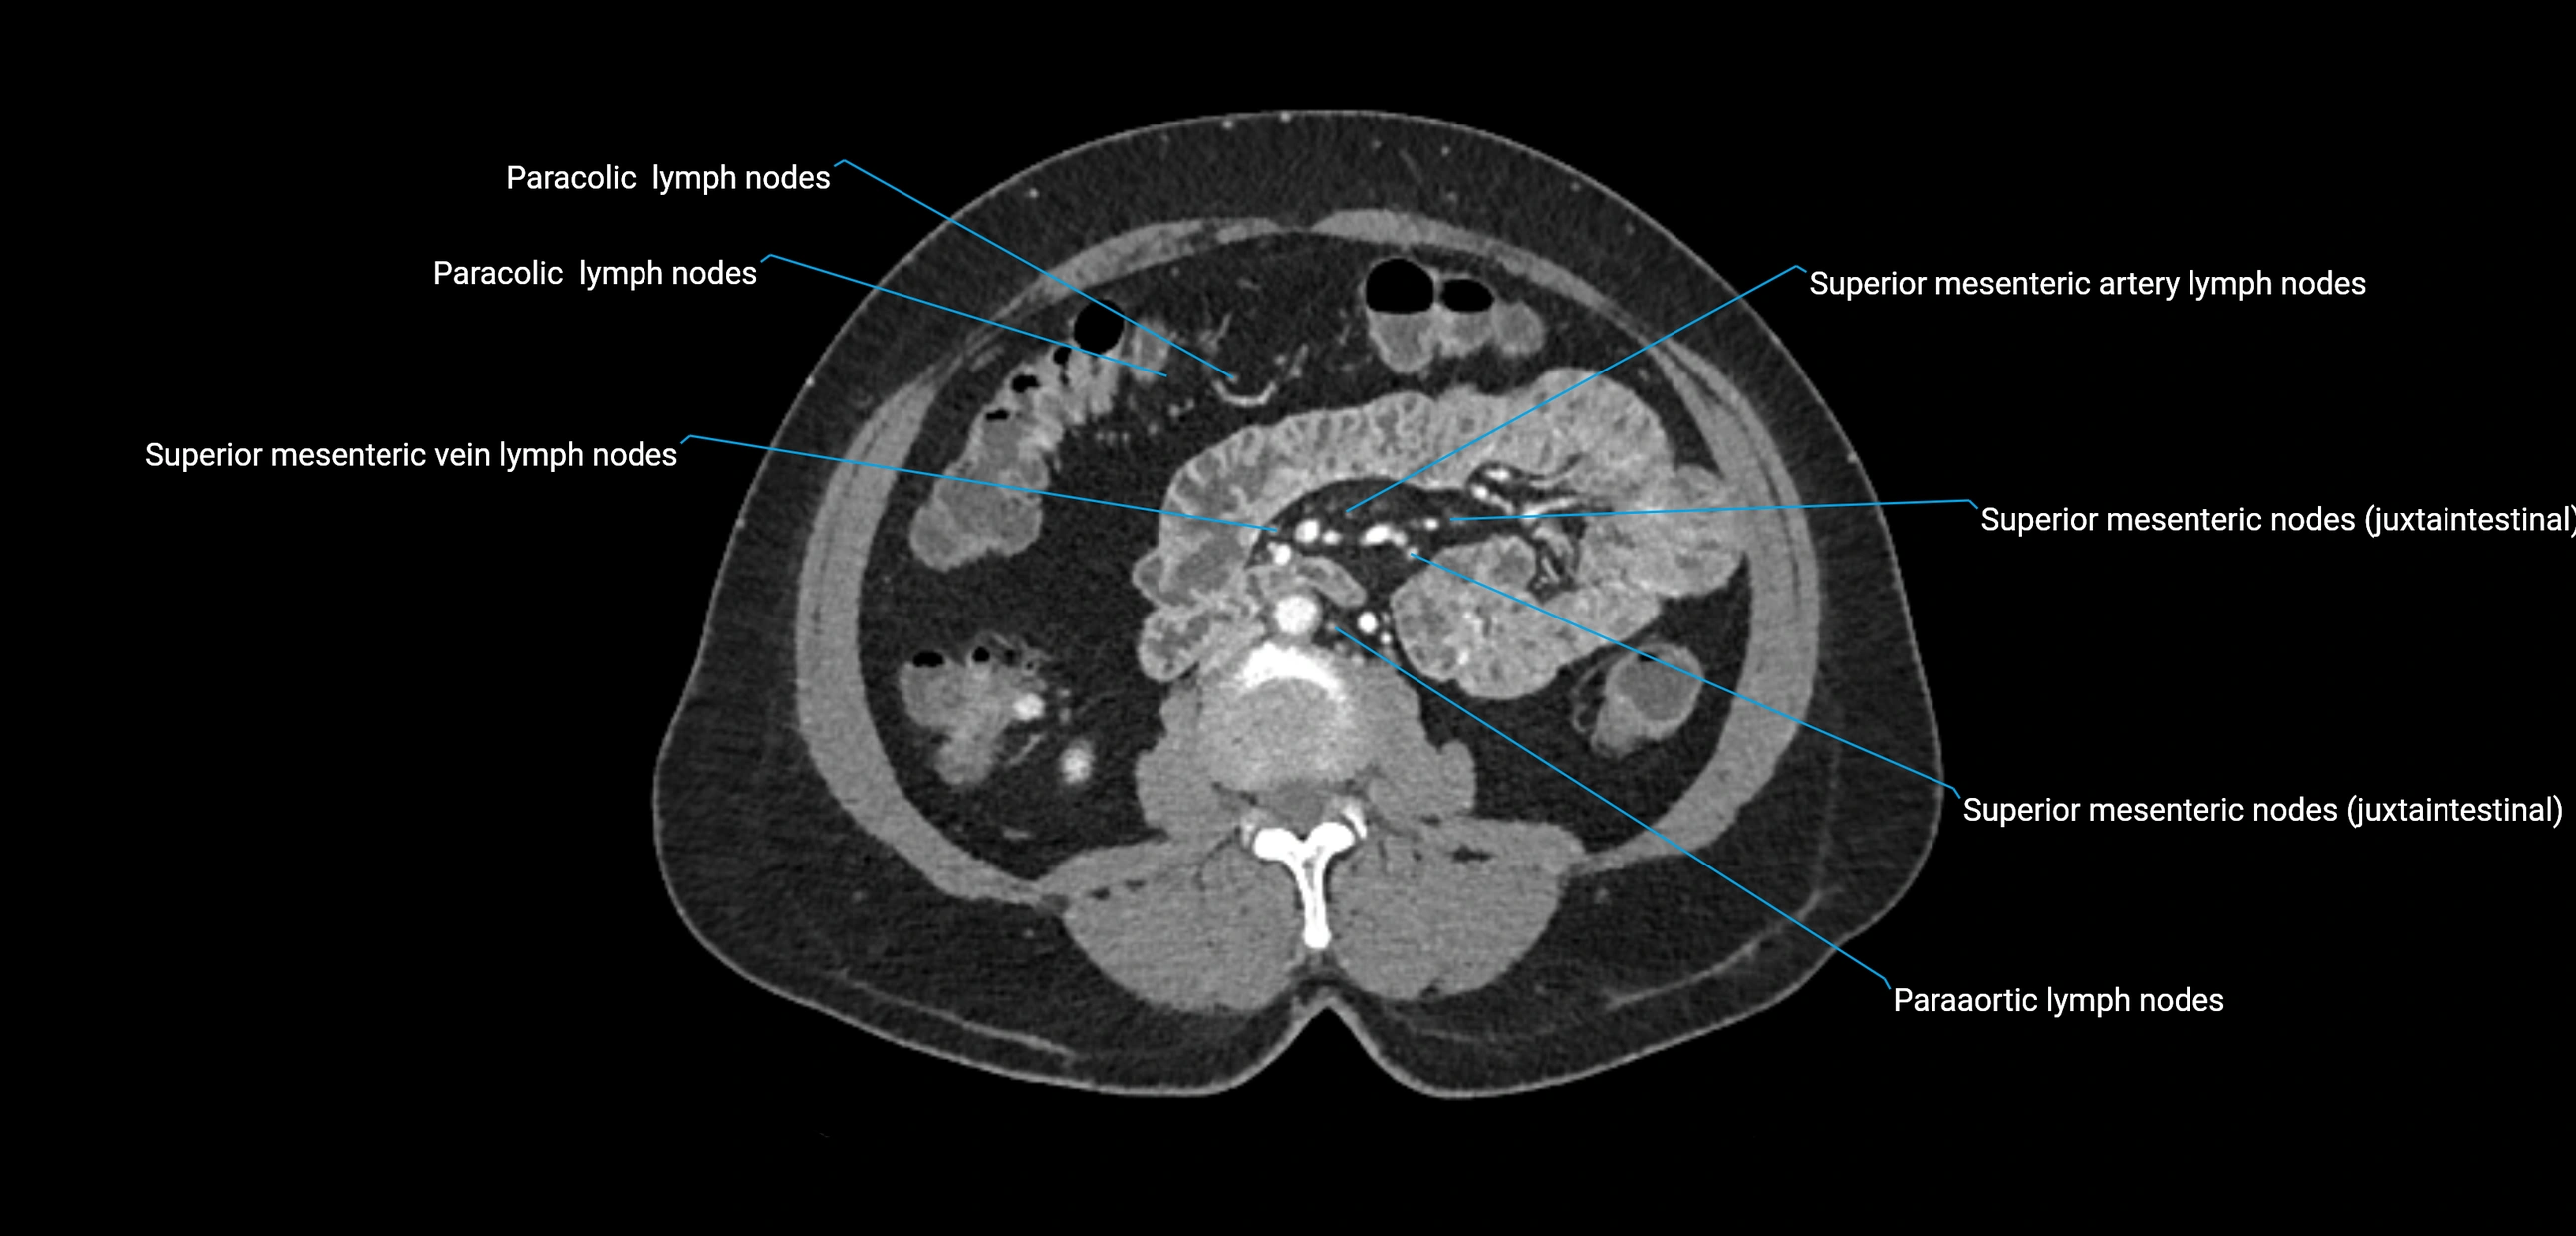

CT image

image